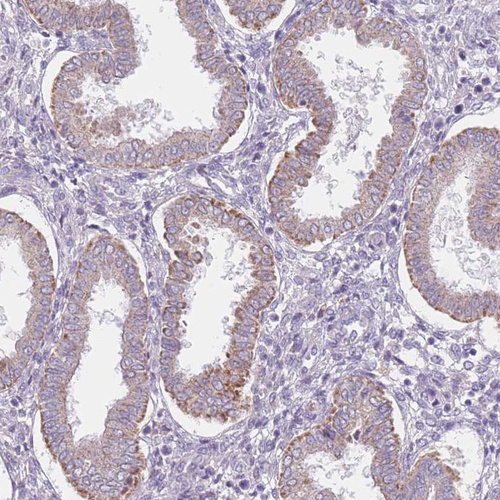

Immunohistochemical staining of human endometrium shows moderate cytoplasm granular positivity in glandular cells.